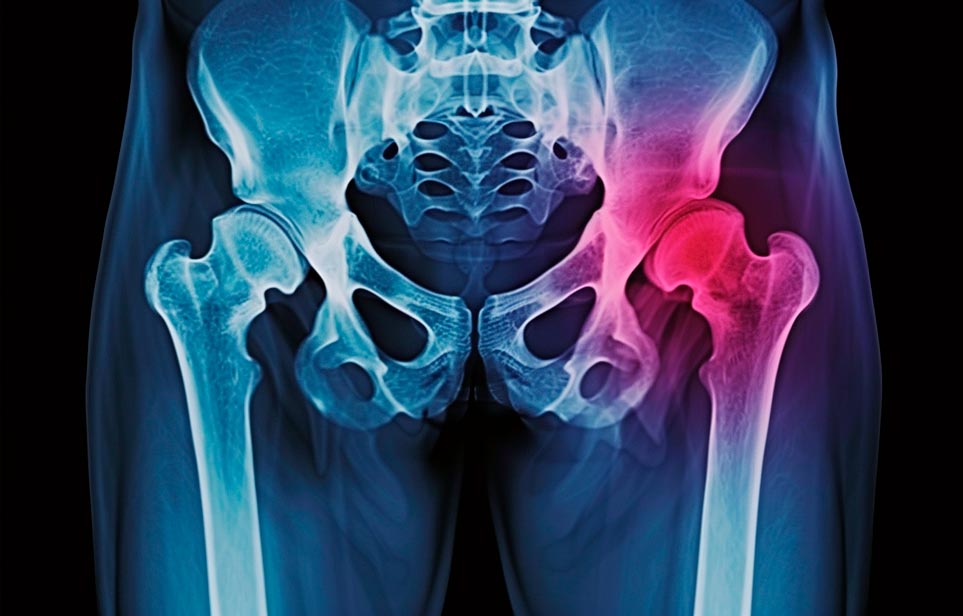

Эффективная и профессиональная реабилитация после перелома шейки бедра в Арзамасе осуществляется по демократичным ценам лучшими специалистами современной медицинской клиники «Заботливые люди» с применением персонального подхода к каждому пожилому человеку с такой тяжёлой травмой бедренной кости ноги. В процессе осуществления такой специализированной услуги все наши пациенты имеют возможность получения качественного и достойного обслуживания, эффективного восстановления. Лучший дом престарелых позаботиться о Вашем близком человеке.

Такая травма в большей части случаев возникает у граждан преклонного возраста. При её появлении на протяжении длительного времени сохраняются болевые и неприятные ощущения в области паха, при которых серьёзно ухудшается качество жизни, возникает множество последствий для его жизни и здоровья.

По какой симптоматике можно определить перелом шейки бедра?

Выявить его можно по возникновению следующей тревожной симптоматики:

- Визуально повреждённая нога сокращается на несколько сантиметром из-за сокращения мышц.

- Стопа выворачивается наружу.

- В лежачем положении человек не может поднять ногу.

При такой симптоматике важно незамедлительно обращаться к специалистам для получения всей необходимой помощи, терапии и восстановления после перелома шейки бедра. Если не оказать помощи старику, то это приведёт к гноению, инвалидности, иным видам осложнений.